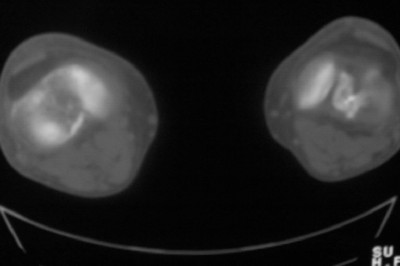

标题: CT8024:会诊!!!男 60 岁 双漆关节疼痛半年,进行性加重 [打印本页]

患者男 60 岁 双漆关节疼痛半年,进行性加重.

左侧股骨下端骨梗死

右股骨内髁关节面下多个不规则小囊变,边缘有明显硬化边,.......考虑: 1.关节面下骨囊变.  2.类风湿关节炎?   3.血友病?

右侧髁间隆突变尖,软骨下假囊肿形成,结合病人年龄较大,首先考虑退行性骨关节病。关节周围软组织未见明显异常,病人单单一双膝关节出现症状,不太支持类风湿性关节炎,可结合化验室检查。